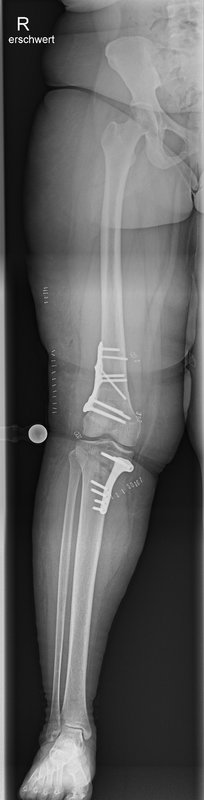

Tibiakopf Fraktur

Die arthroskopisch assistierte Frakturversorgung (insbesondere am Tibiakopf) im Rahmen von Band- bzw. Kombinationsverletzungen ist ebenfalls ein Schwerpunkt der Abteilung. Der ärztliche Direktor PD Dr. med. Schlumberger ist im DKG-Komitee „Frakturen“ vertreten.

Beinachsfehlstellungen

Manchmal liegen Beschwerden Fehlstellungen zu Grunde – sei es im Sinne eines „O-Beins“ bzw. eines „X-Beins“, aber auch eine Rotationsfehlstellung kann ursächlich für Beschwerden des Kniegelenkes sein. Gerade bei Knorpelschädigungen und Arthrose ist eine Fehlstellung mit konsekutiver Überlastung einer Gelenkhälfte oftmals ursächlich. Durch den Ausgleich der Fehlstellung wird die Biomechanik des Gelenkes wieder hergestellt und das betroffene Areal entlastet. Wir bieten Umstellungen in allen Ebenen (O-Bein, X-Bein, Rotationsfehlstellungen, pathologischer Slope, …) an. Oft ist es sogar möglich, dass eine notwendige endoprothetische Versorgung nochmals lange hinausgezögert werden kann, was vor allem jungen Patienten zu Gute kommt.